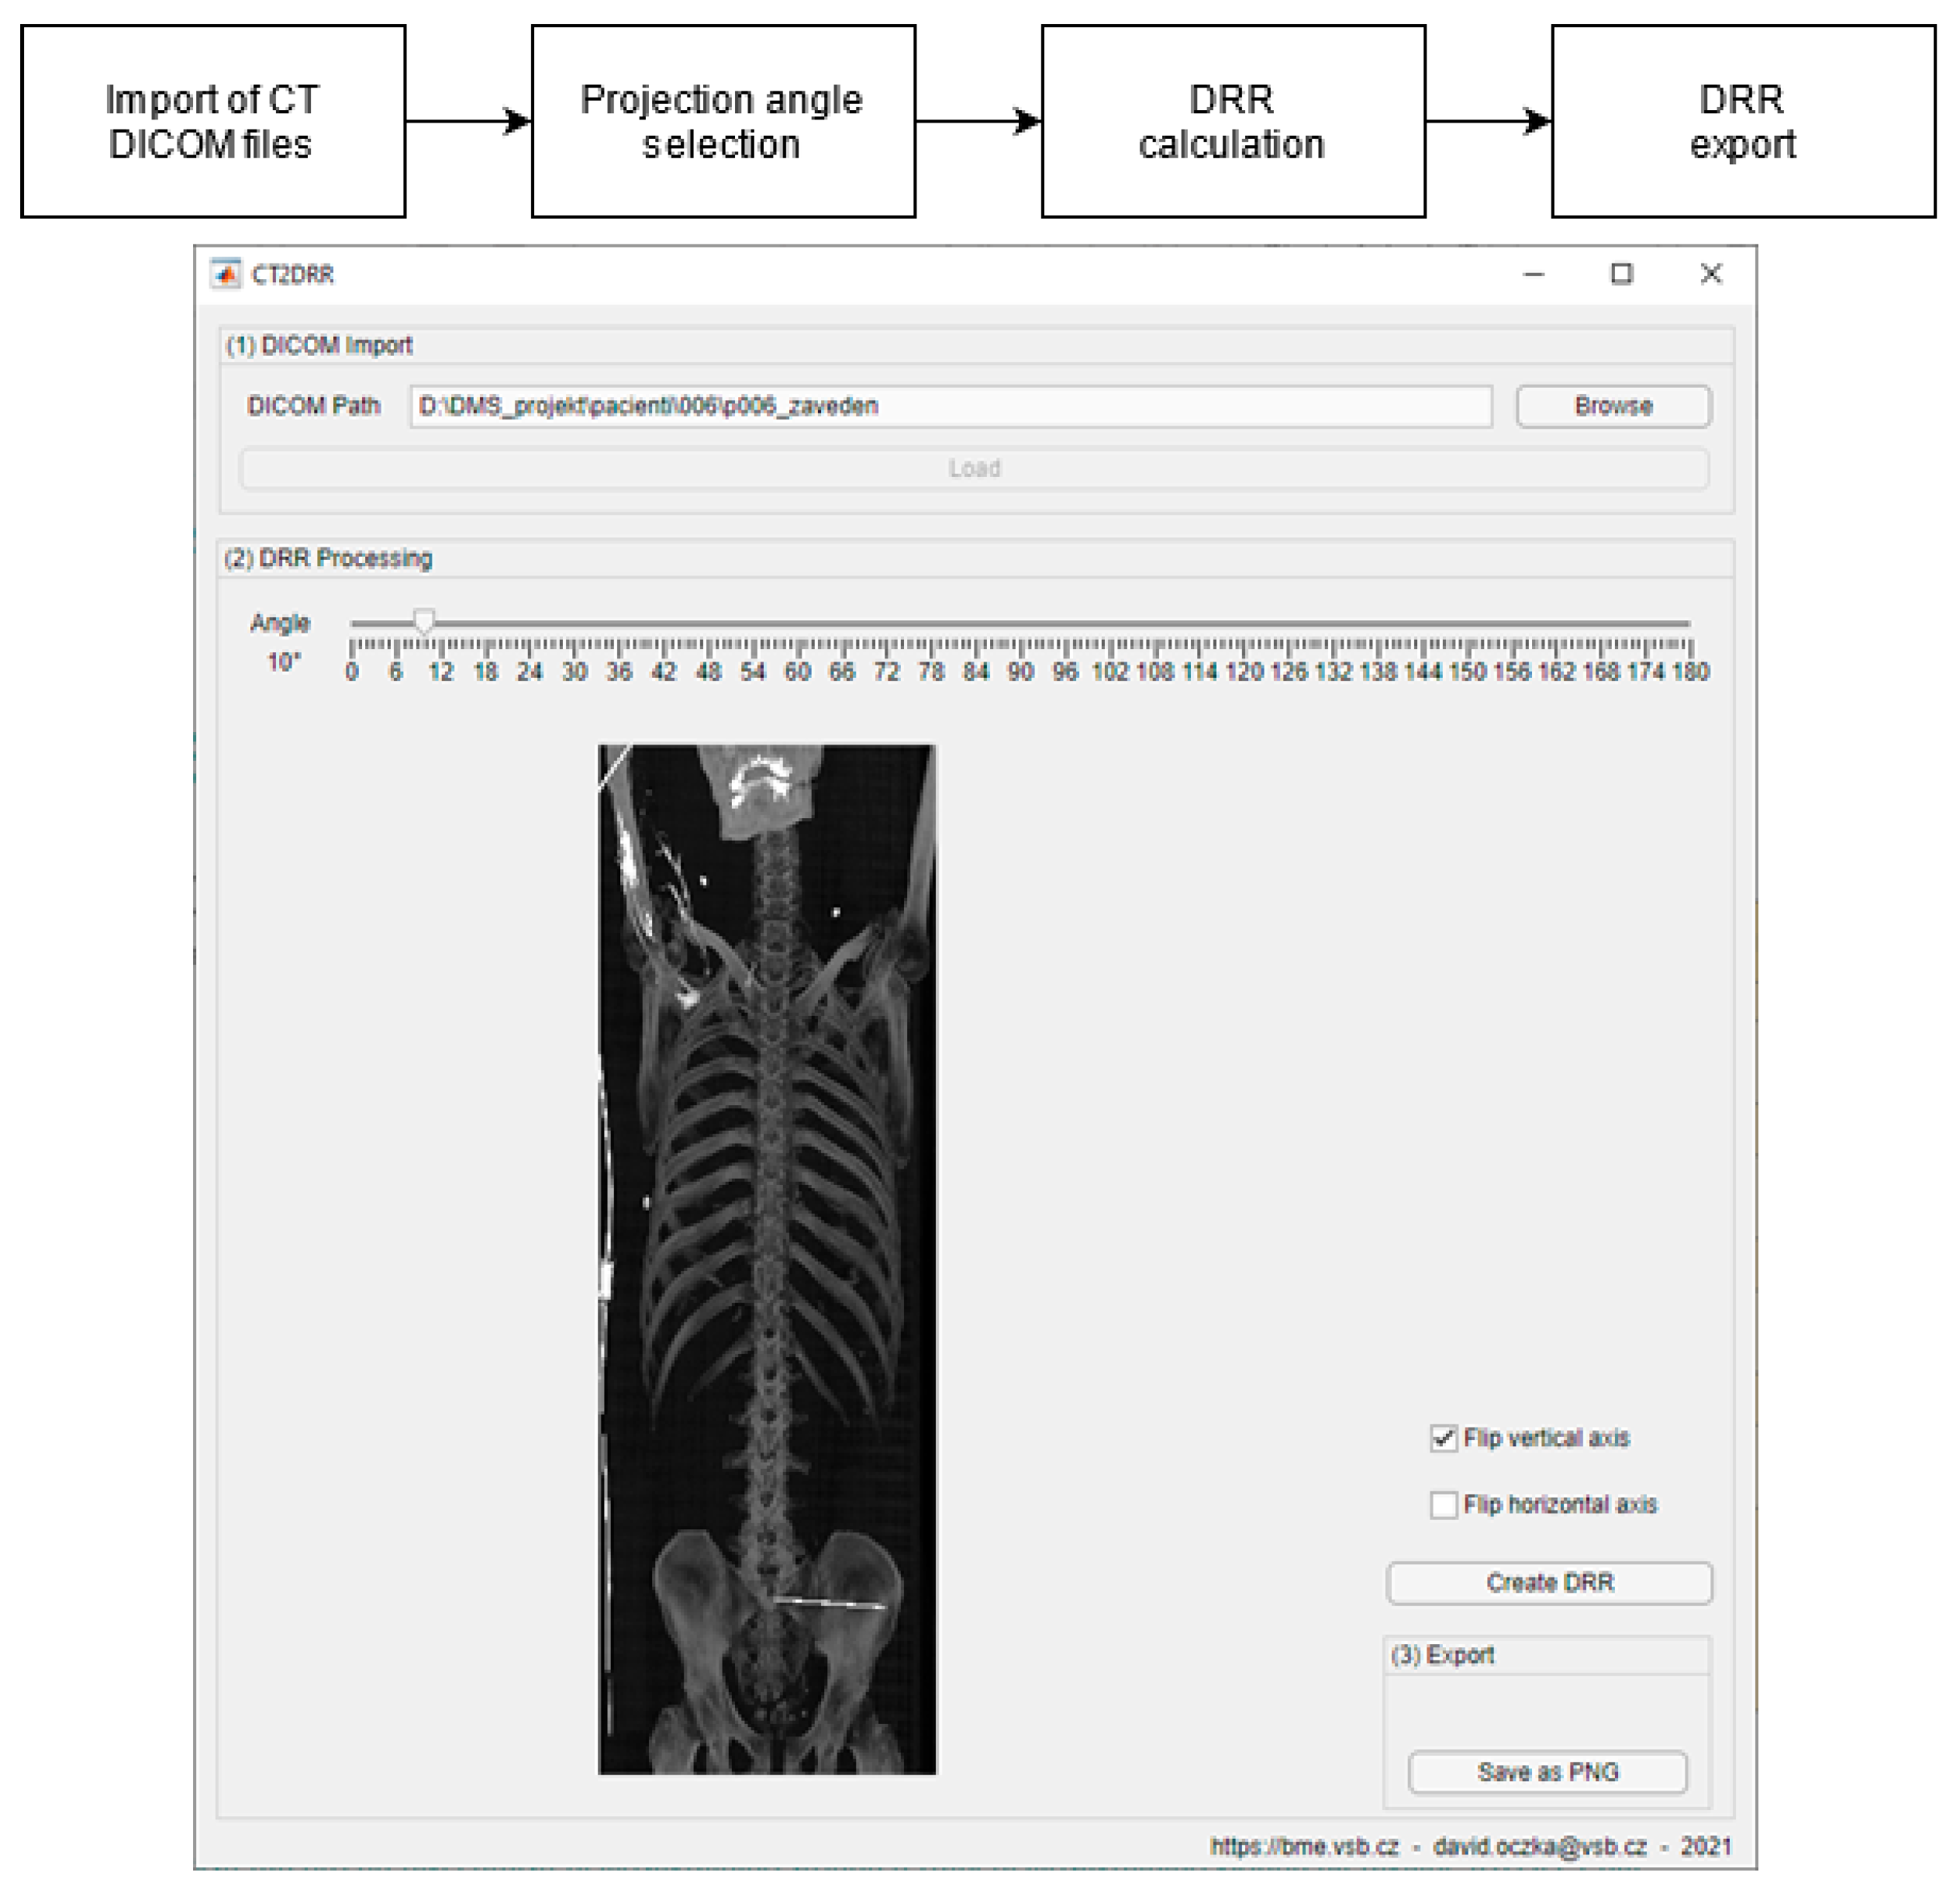

3.2. DDR Projection Generation (CT2DDR)

- Generation of digitally reconstructed radiograph (DRR) projections